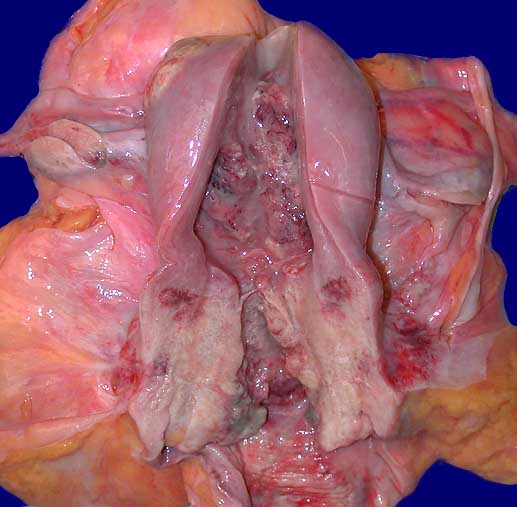

Zervixkarzinom und Endometriumkarzinom

Längsschnitt durch den Uterus. Die Zervix ist aufgetrieben durch einen gelblich-weissen Tumor. Exophytischer Tumor im Bereich des Uteruscavum mit Infiltration bis unter die Serosa. Angeschnittenes tumorfreies Ovar.

Histologie: endometrioides Karzinom des Cavums und Plattenepithelkarzinom der Zervix.